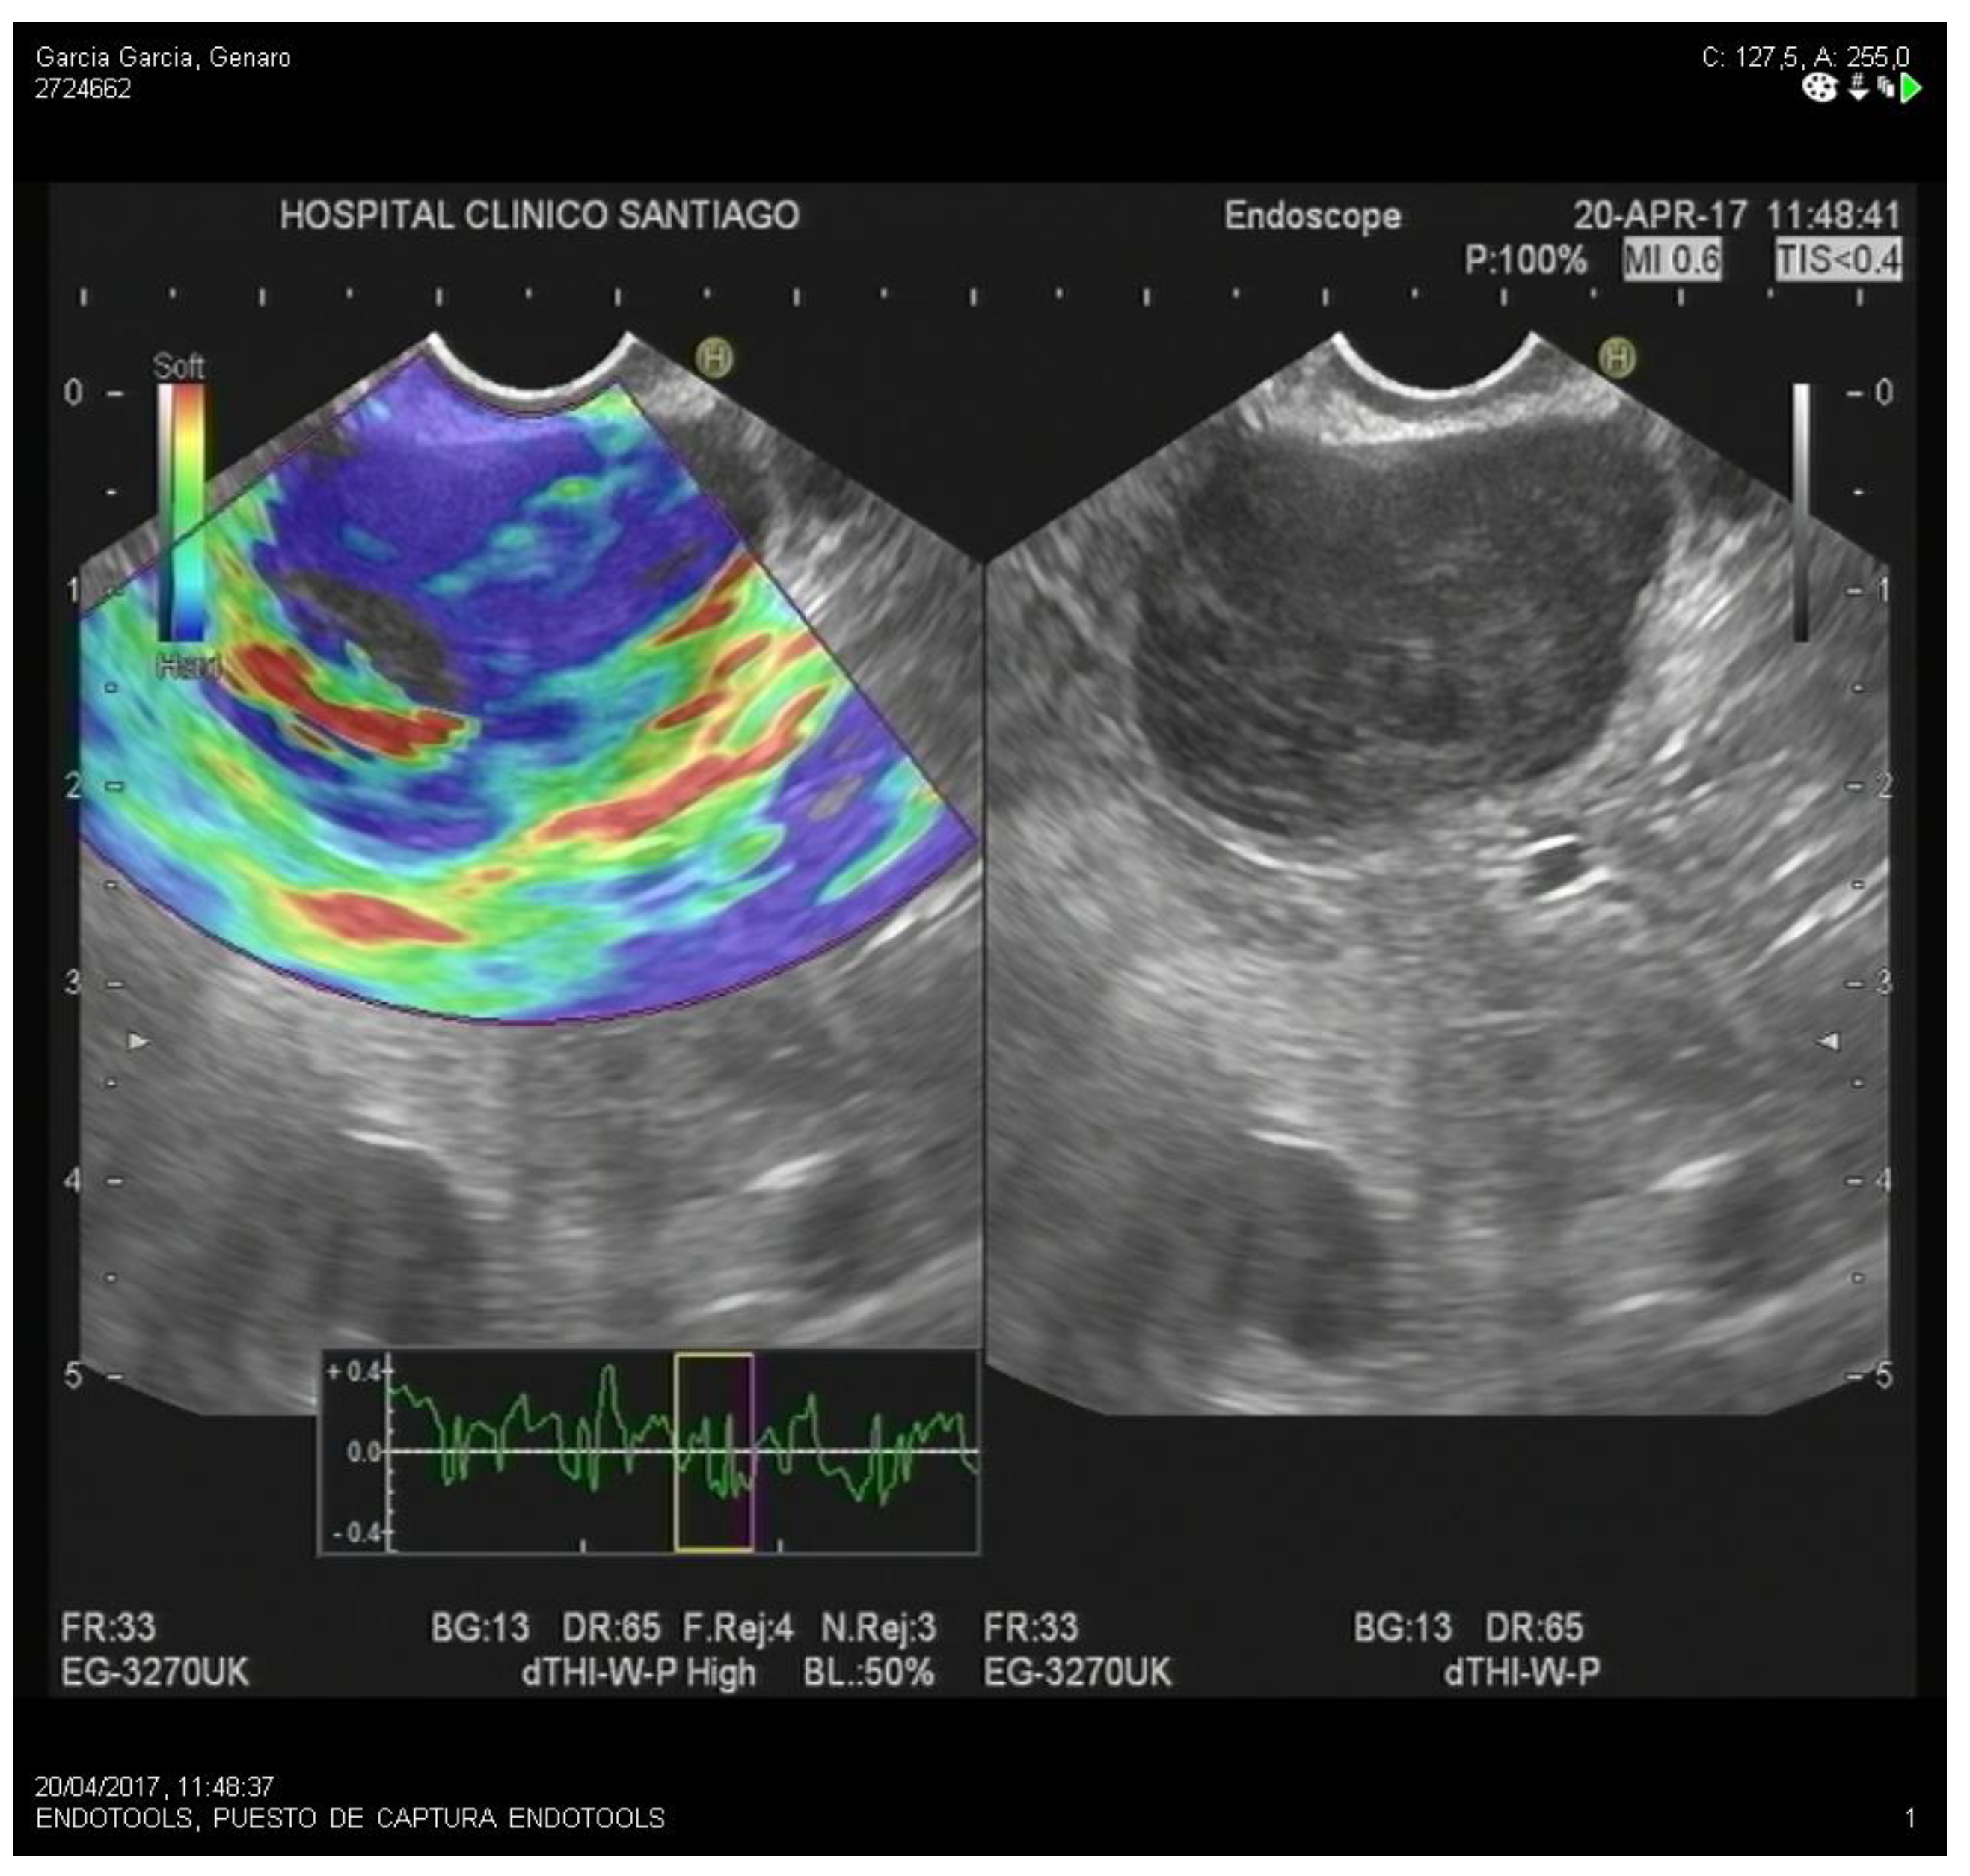

2.1. Strain Elastography

- Qualitative Strain Elastography

- Quantitative Strain Elastography

- -

- Strain Histogram

- Strain ratio

4.1. Differential Diagnosis of Solid Pancreatic Lesions